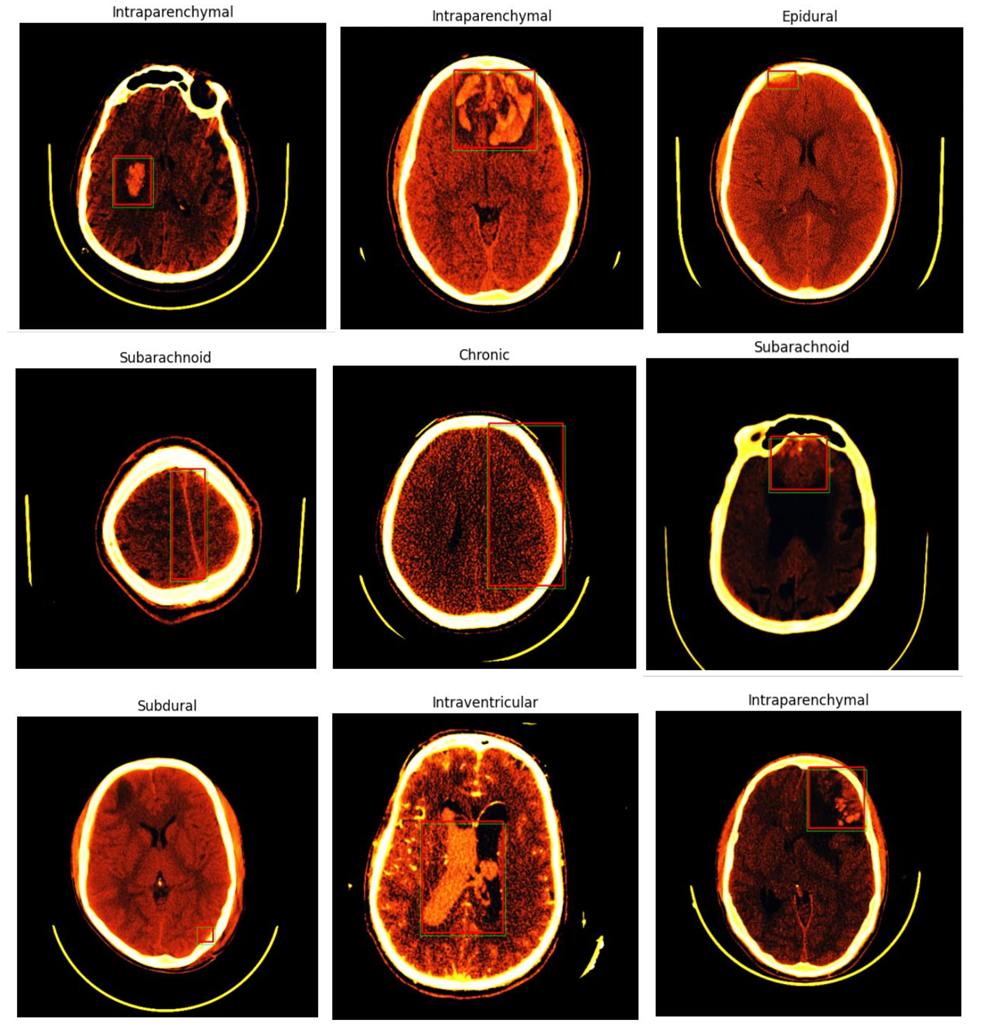

Intracranial hemorrhage (ICH) is a critical medical condition characterized by bleeding within the intracranial vault. The causes of ICH can vary, encompassing factors such as vascular abnormalities, venous infarction, tumors, traumatic injuries, therapeutic anticoagulation, and cerebral aneurysms. Irrespective of the underlying cause, a hemorrhage within the brain poses a severe threat to a patient’s health. Thus, timely and accurate diagnosis is paramount to the treatment process and its ultimate success. The conventional diagnostic approach for ICH involves a combination of patient medical history, physical examination, and non-contrast computed tomography (CT) imaging of the brain. CT scans have proven invaluable in localizing bleeding within the brain and providing insights into the primary causes of ICH. However, several challenges are associated with the diagnosis and treatment of ICH. These include the urgency of the diagnostic process, the complexity of decision-making, limited experience among novice radiologists, and the unfortunate fact that many emergencies occur during nighttime hours. Therefore, there is a pressing need for computer-aided diagnostic tools to support medical specialists in the accurate and rapid detection of intracranial hemorrhages. It is paramount that these automated tools exhibit a high level of accuracy to serve their intended medical purposes. Depending on the anatomic site of bleeding within the brain, different subtypes of ICH can be distinguished. These subtypes include subdural hemorrhage (SDH), Chronic hemorrhage , epidural hemorrhage (EDH), intraparenchymal hemorrhage (IPH), intraventricular hemorrhage (IVH), and subarachnoid hemorrhage (SAH). Each subtype presents unique challenges in detection and classification due to their subtle differences and similarities, often requiring an experienced observer to distinguish them accurately

In this post, we present a method for detecting various subtypes of intracranial hemorrhage in brain CT scans. Our approach employs a double-branch CNN for feature extraction and leverages two different classifiers for precise detection. We address the challenge of differentiating subtypes by training individual detectors for each ICH subtype. Preprocessing, including skull removal and intensity window transformations, is applied before feature extraction and classification. Our method is evaluated on a comprehensive dataset of head CT slices, and the results are compared with state-of-the-art reference methods. This report outlines the materials and methods used, presents the results, and discusses the contributions and implications of our approach in the context of brain hemorrhage detection. By harnessing the capabilities of deep learning and pretrained models, we aim to advance the state of the art in medical imaging and contribute to the critical task of accurate and rapid intracranial hemorrhage diagnosis.

Our model architecture combines two powerful deep-learning components: a ResNet-based classification model and a YOLO-based object detection model.

The first component, built on the ResNet50V2 architecture, serves as the backbone for classifying different types of brain hemorrhages. ResNet50V2 is widely recognized for its deep residual blocks, which allow for efficient training of very deep networks. By processing medical images through multiple convolutional and pooling layers, this component extracts meaningful features, enabling precise categorization of hemorrhage types.

The second component, based on the YOLO (You Only Look Once) architecture, specializes in the precise localization of hemorrhages within brain scans. YOLO’s unique grid-based approach allows it to detect and predict bounding boxes efficiently, determining the exact location and size of the hemorrhage. Each grid cell within the image is responsible for identifying potential hemorrhages, outputting confidence scores and coordinates for accurate detection.

By combining these two models, our architecture provides a comprehensive solution for brain hemorrhage diagnosis. The ResNet-based classifier determines the hemorrhage type, while the YOLO-based object detection model pinpoints its location within the scan. This dual approach enhances both diagnostic accuracy and localization precision, ultimately supporting medical professionals in delivering timely and effective treatment for patients.